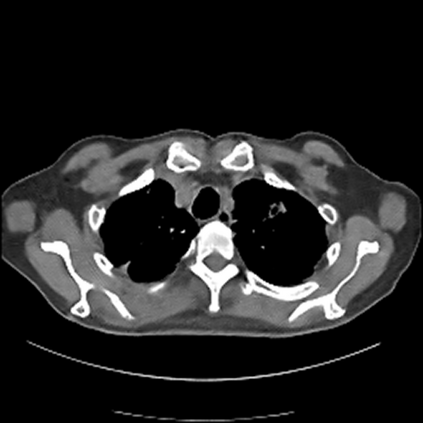

Sparse-view computed tomography (CT) -- using a small number of projections for tomographic reconstruction -- enables much lower radiation dose to patients and accelerated data acquisition. The reconstructed images, however, suffer from strong artifacts, greatly limiting their diagnostic value. Current trends for sparse-view CT turn to the raw data for better information recovery. The resultant dual-domain methods, nonetheless, suffer from secondary artifacts, especially in ultra-sparse view scenarios, and their generalization to other scanners/protocols is greatly limited. A crucial question arises: have the image post-processing methods reached the limit? Our answer is not yet. In this paper, we stick to image post-processing methods due to great flexibility and propose global representation (GloRe) distillation framework for sparse-view CT, termed GloReDi. First, we propose to learn GloRe with Fourier convolution, so each element in GloRe has an image-wide receptive field. Second, unlike methods that only use the full-view images for supervision, we propose to distill GloRe from intermediate-view reconstructed images that are readily available but not explored in previous literature. The success of GloRe distillation is attributed to two key components: representation directional distillation to align the GloRe directions, and band-pass-specific contrastive distillation to gain clinically important details. Extensive experiments demonstrate the superiority of the proposed GloReDi over the state-of-the-art methods, including dual-domain ones. The source code is available at https://github.com/longzilicart/GloReDi.